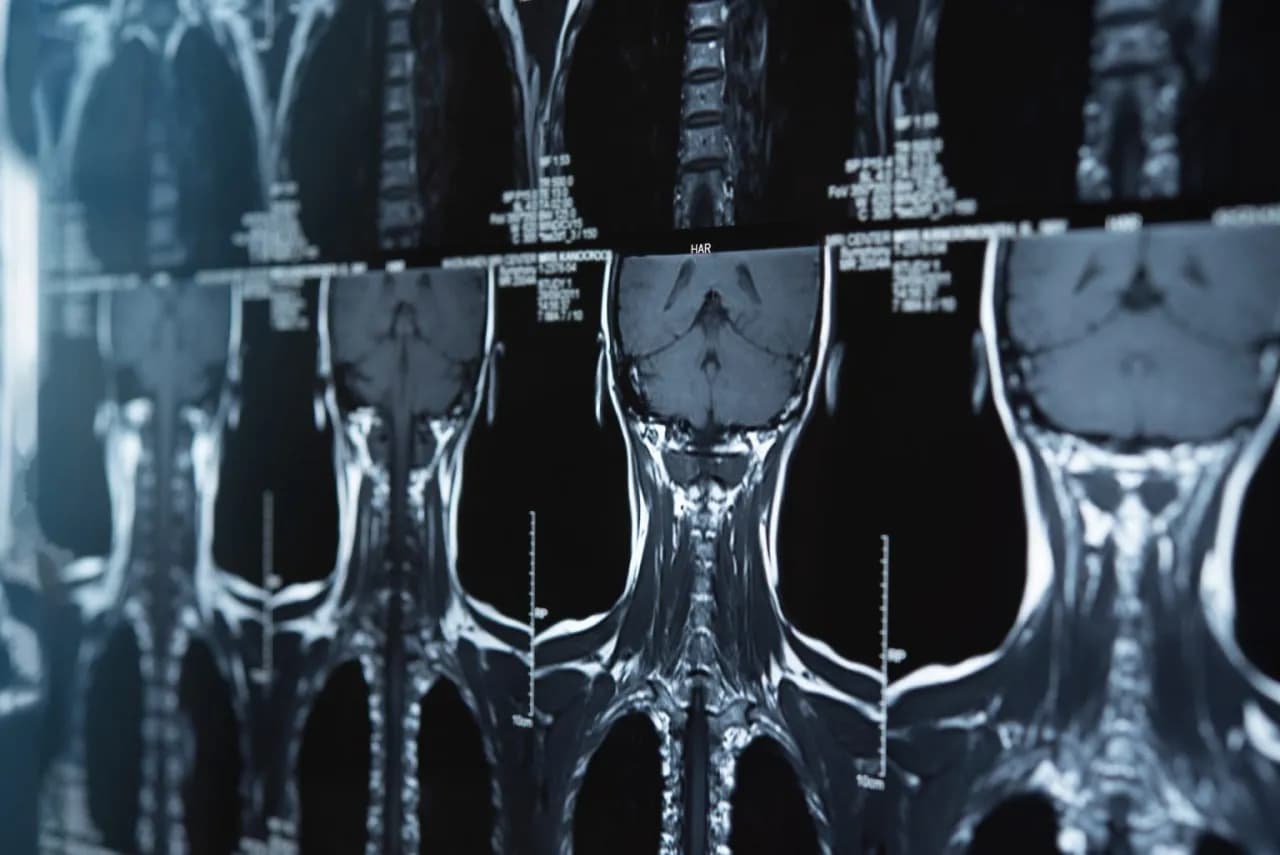

Rezonans odcinka szyjnego to ważne badanie diagnostyczne, które pozwala na dokładną ocenę stanu kręgosłupa szyjnego. Wiele osób zastanawia się, jak długo trwa takie badanie. Czas trwania rezonansu magnetycznego odcinka szyjnego zazwyczaj wynosi od 15 do 45 minut, ale w praktyce najczęściej trwa około 20–30 minut. Warto jednak pamiętać, że czas ten może się różnić w zależności od specyfiki przypadku oraz rodzaju używanego sprzętu.

Rezonans magnetyczny odcinka szyjnego to badanie, które zazwyczaj trwa od 15 do 45 minut. Czas ten może się różnić w zależności od specyfiki przypadku oraz rodzaju używanego sprzętu. W większości przypadków badanie zajmuje około 20–30 minut, co jest typowym czasem dla standardowych procedur.